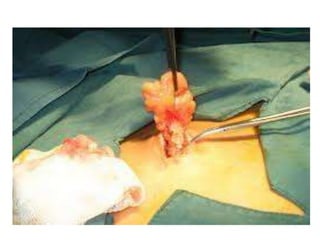

Surgical excision of Lipomas

 They can be left alone. They may need to be removed

for cosmetic reasons, because of compression of

surrounding structures or if the diagnosis is uncertain

 Lipomas are normally removed by simple excision. The removal

can often be done under local anaesthetic, and takes fewer than

30 minutes. This cures the great majority of cases, with about 1–

2% of lipomas recurring after excision.

 Because lipomas generally do not infiltrate into surrounding

tissue, they can usually be shelled out easily duringexcision.

 Minimal scarring can be achieved with a technique called

segmental extraction - a small stab incision followed by blind

dissection of the lipoma and extraction in a segmental fashion

 Liposuction is another option if the lipoma is softand